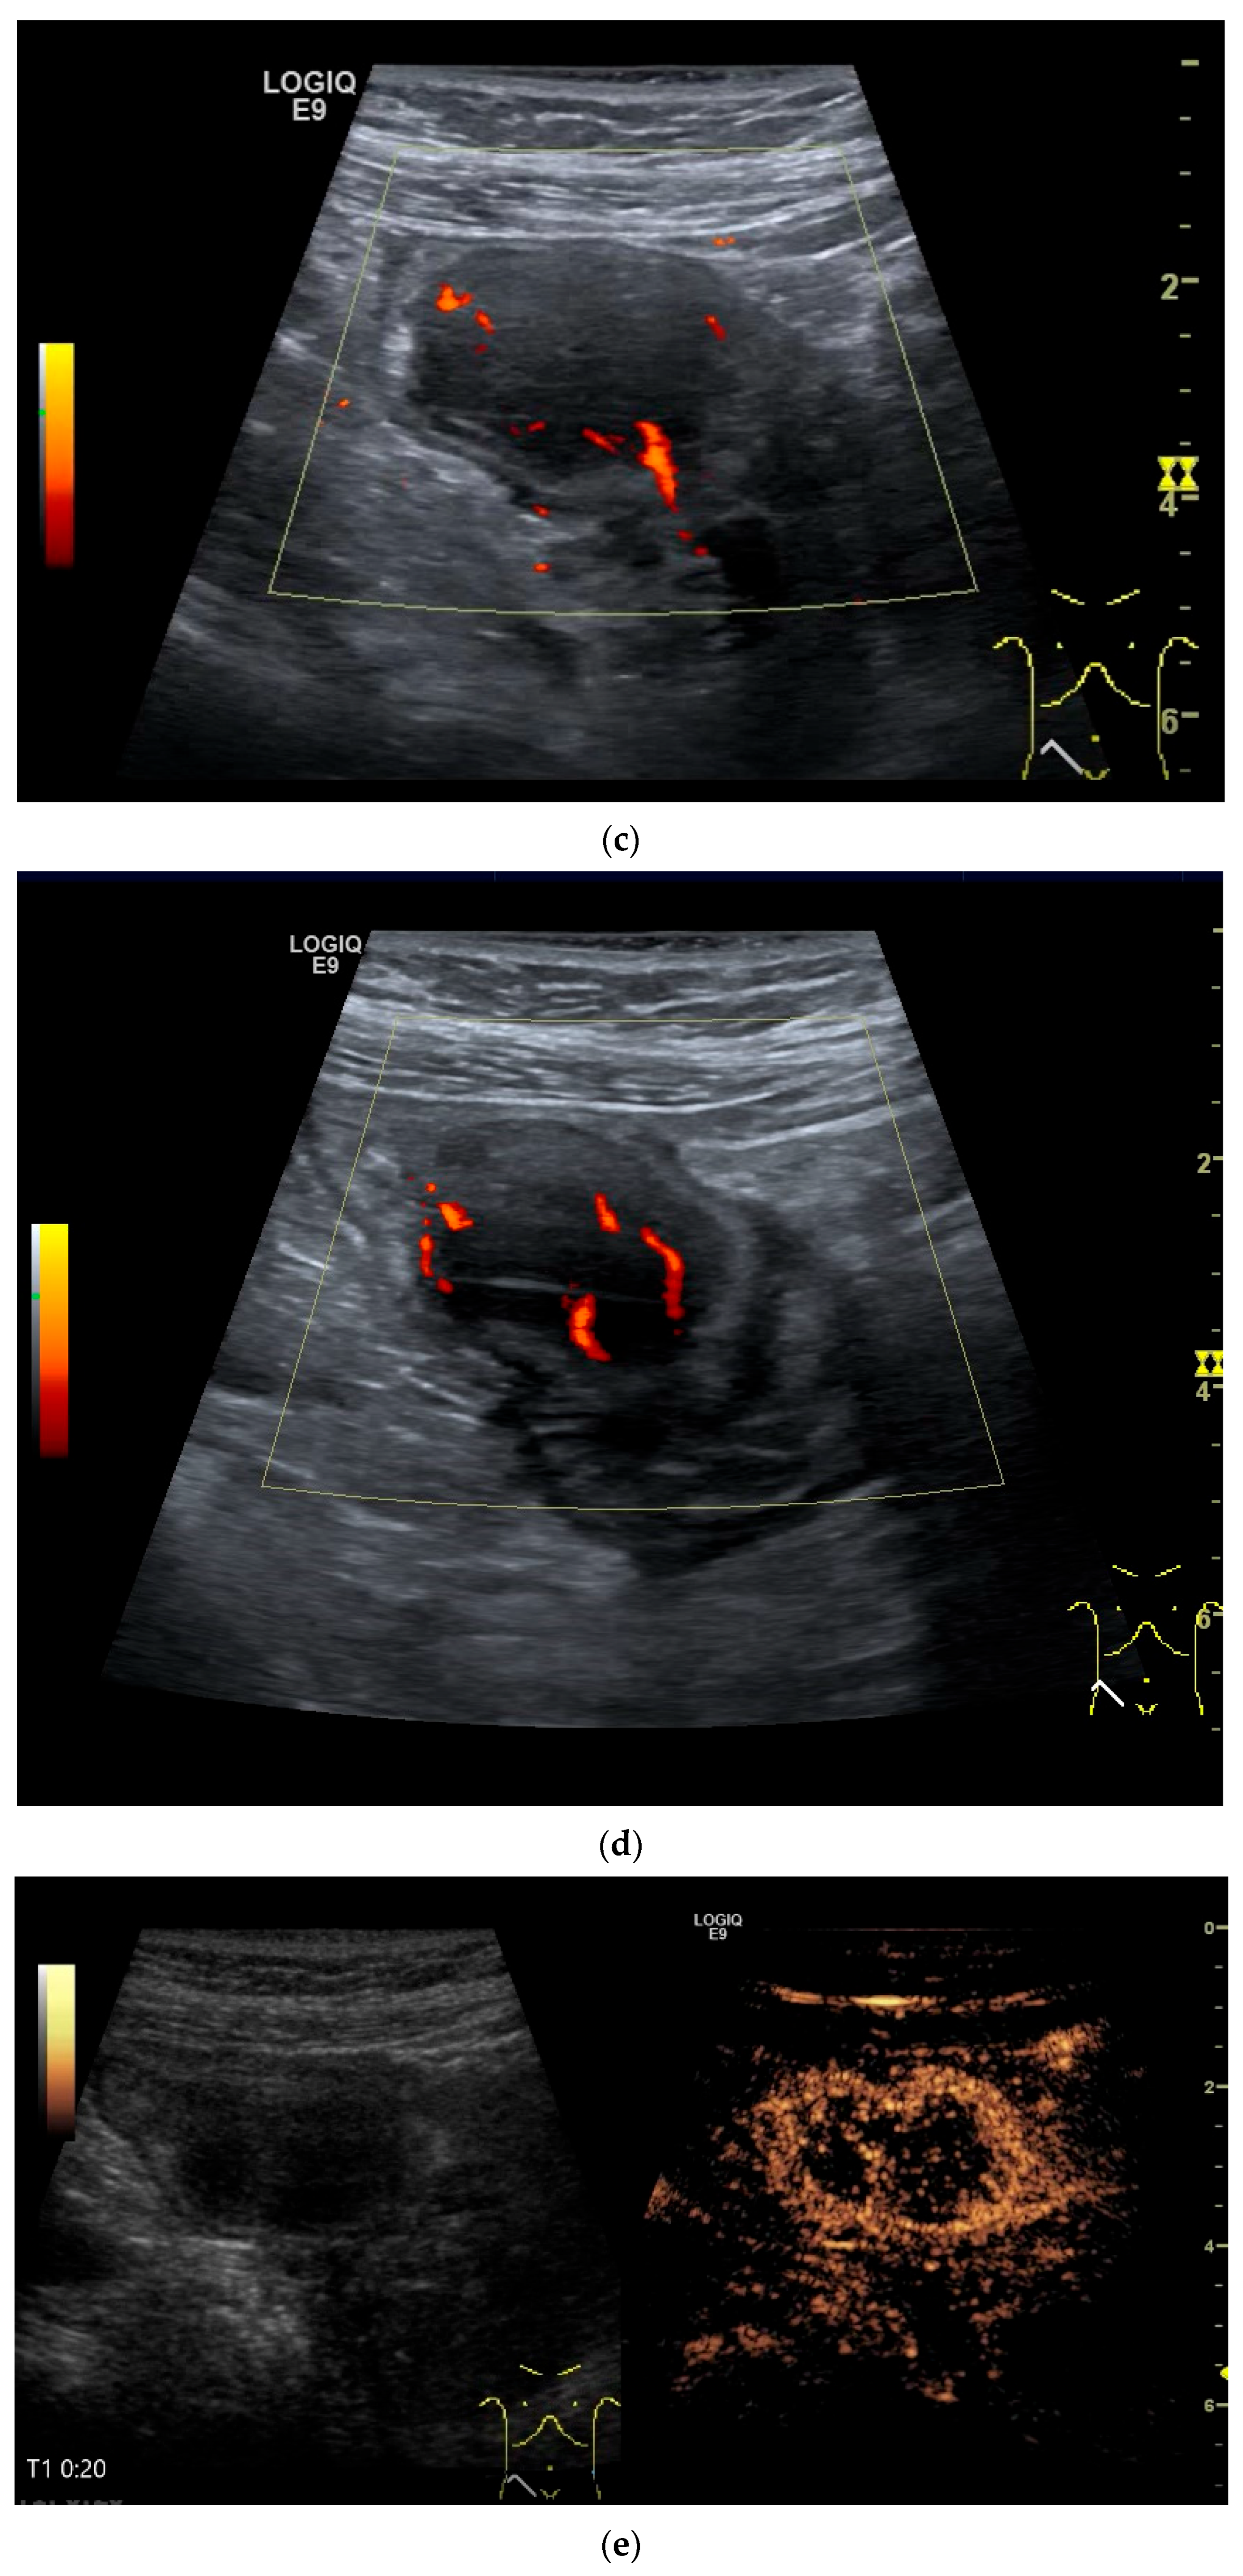

- Zhao, J.Y.; Zhuang, H.; Luo, Y.; Su, M.G.; Xiong, M.L.; Wu, Y.T. Double contrast-enhanced ultrasonography of a small intestinal neuroendocrine tumor: A case report of a recommendable imaging modality. Precis. Clin. Med. 2020, 3, 147–152. [Google Scholar] [CrossRef]

| Neuroendocrine tumor | Small, nodular hypoechoic wall thickenings, mostly in the submucosa with spreading into the other layers. Usually with small vessels on CDI. Regionally enlarged lymph nodes. Multilocular manifestations are possible. |